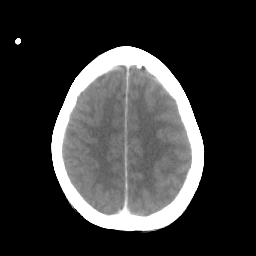

Metastatic bronchogenic carcinoma: Roentgen-ray CT -- Slice #17

[Home][Help][Clinical] Slice 17